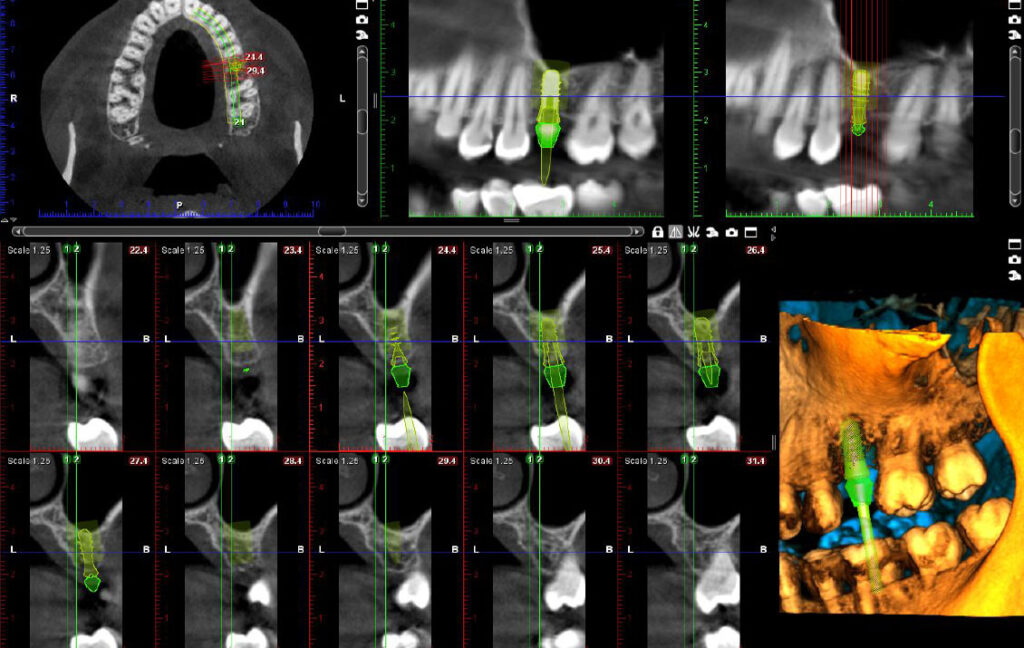

06. Implant plan

Primena CBCT snimka u oblasti:

Maksilofacijalna Hirurgija

Oralna Hirurgija

Implantologija